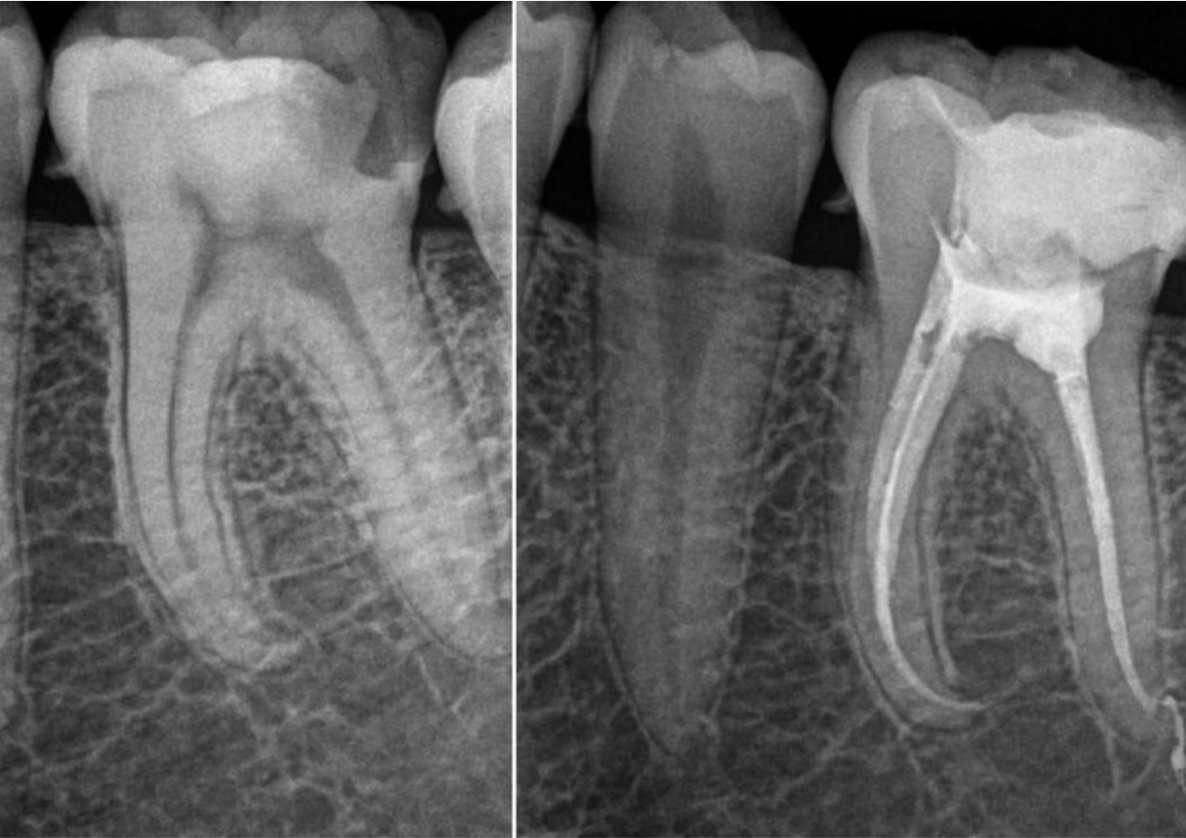

En una estancia clínica conmigo es habitual ver casos relacionados con tratamientos endodónticos, que no son sólo la endodoncia, si no recubrimientos pulpares, directo e indirecto; apicoformación y lo más importante, el diagnóstico clínico.

Cuando sabes diagnosticar es un antes y un después. Rehabilitación del diente endodonciado, básico para el éxito del tratamiento.

¿Qué tratamientos podrás presenciar? Tratamientos endodónticos que no son sólo la endodoncia si no recubrimientos pulpares, directo e indirecto; apicoformación y lo más importante el diagnóstico clínico